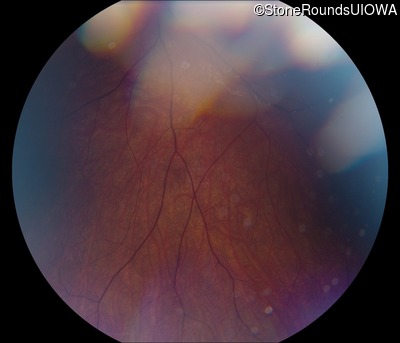

Fundus Photography - Right - 20/40 +1

Exemplar

Fundus Photography - Left - 20/50